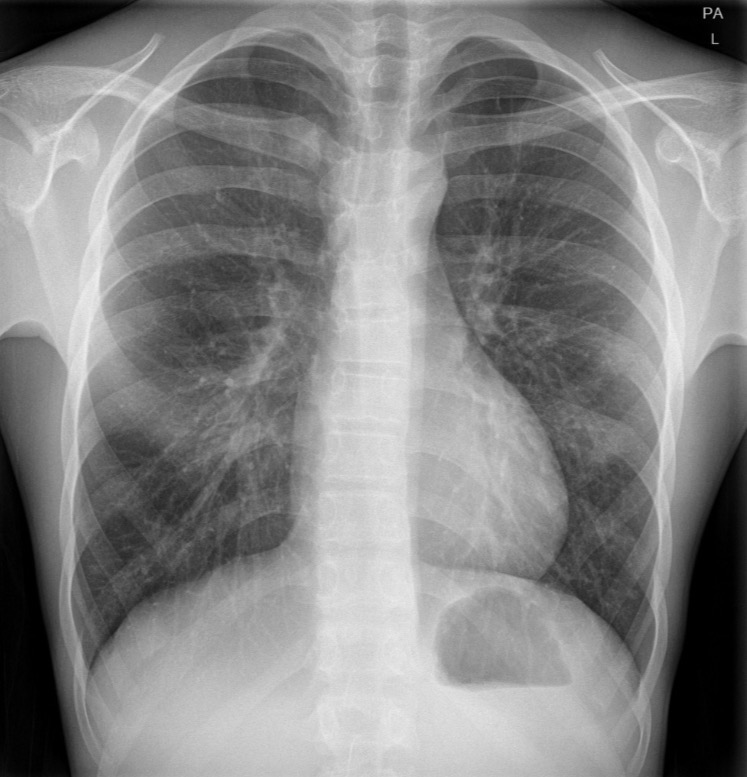

age 15, gender M, pt is acutely breathless and might have a pneumothorax. CXR nl, no consolidation collapse, pneumothorax, or effusion. Nl mediastinal contour and pulmonary vasculature

Normal chest radiograph